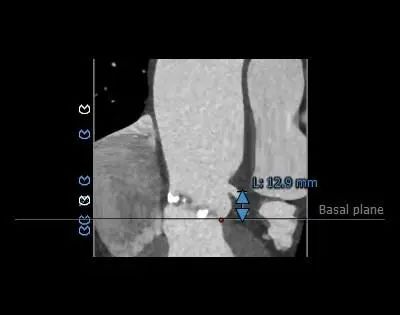

主动脉根部评估

病例特点